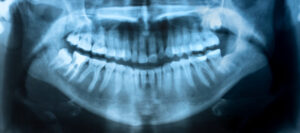

STEP2 精密検査・診断

Dental X-Ray. A panoramic x-ray of a mouth, with intact wisdom teeth, one of which is severely impacted.

治療相談・カウンセリングを経て、セラミック矯正を受けたいと希望される方には、精密検査を実施します。お口の中の写真やレントゲン撮影、歯型取りなどを行った上で診断を下します。その際、虫歯や歯周病などが見つかった場合は、それらの治療を優先します。とくに問題がなければ、診断結果と患者さまのご要望を踏まえた上で、治療計画を立案し、ご説明します。この時点でも何か不安に感じることや疑問に思うことがあれば、気兼ねなくご質問ください。セラミック矯正は、患者さまにとってとても重要な治療となるため、心からご納得いただけるまで丁寧にご説明します。